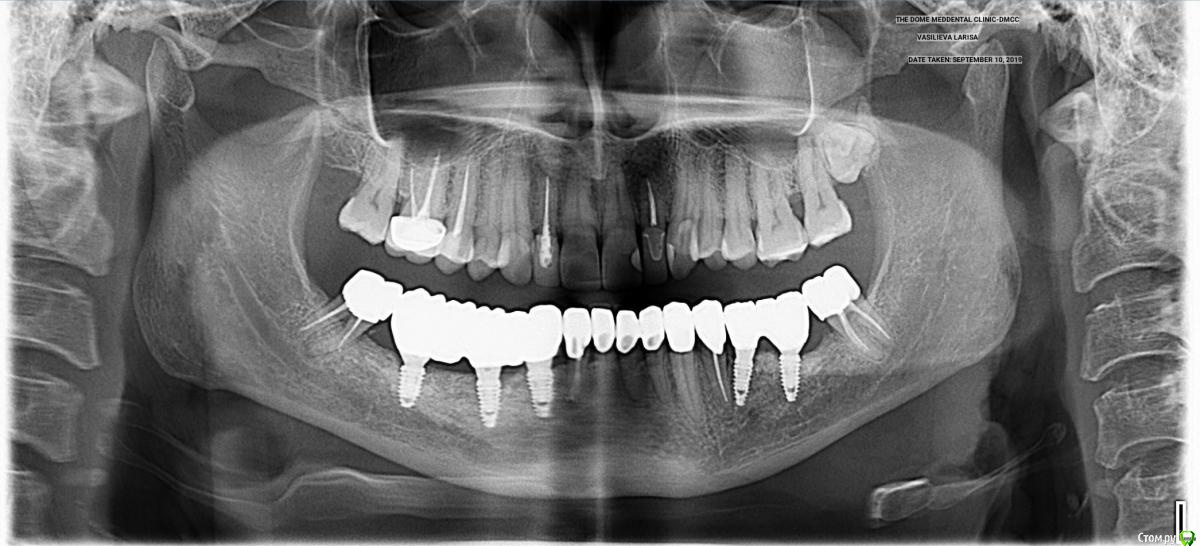

АнтонТЛТ Опубликовано 4 января, 2020 Автор Поделиться Опубликовано 4 января, 2020 Три с половиной года спустя. С другой стороны ситуация была аналогичная и кость восстанавливалась также. 7 Ссылка на комментарий

dentikl Опубликовано 4 января, 2020 Поделиться Опубликовано 4 января, 2020 Три с половиной года спустя. С другой стороны ситуация была аналогичная и кость восстанавливалась также.Вопрос.Импланты ставили непаралельно корням с целью закрутить максимально длинные? Ссылка на комментарий

АнтонТЛТ Опубликовано 4 января, 2020 Автор Поделиться Опубликовано 4 января, 2020 Вопрос.Импланты ставили непаралельно корням с целью закрутить максимально длинные?Никакого сакрального смысла не было именно так ставить)) стараюсь ставить, чтобы шахты имплантатов выходили интропроксимально антагонистам. 35 немного завален, но на протезирование не повлияло. Ссылка на комментарий